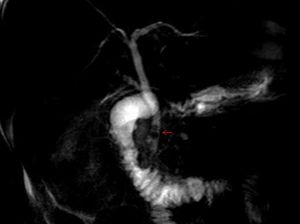

- ERCP

- Should be obtained to confirm the diagnosis and for possible intervention